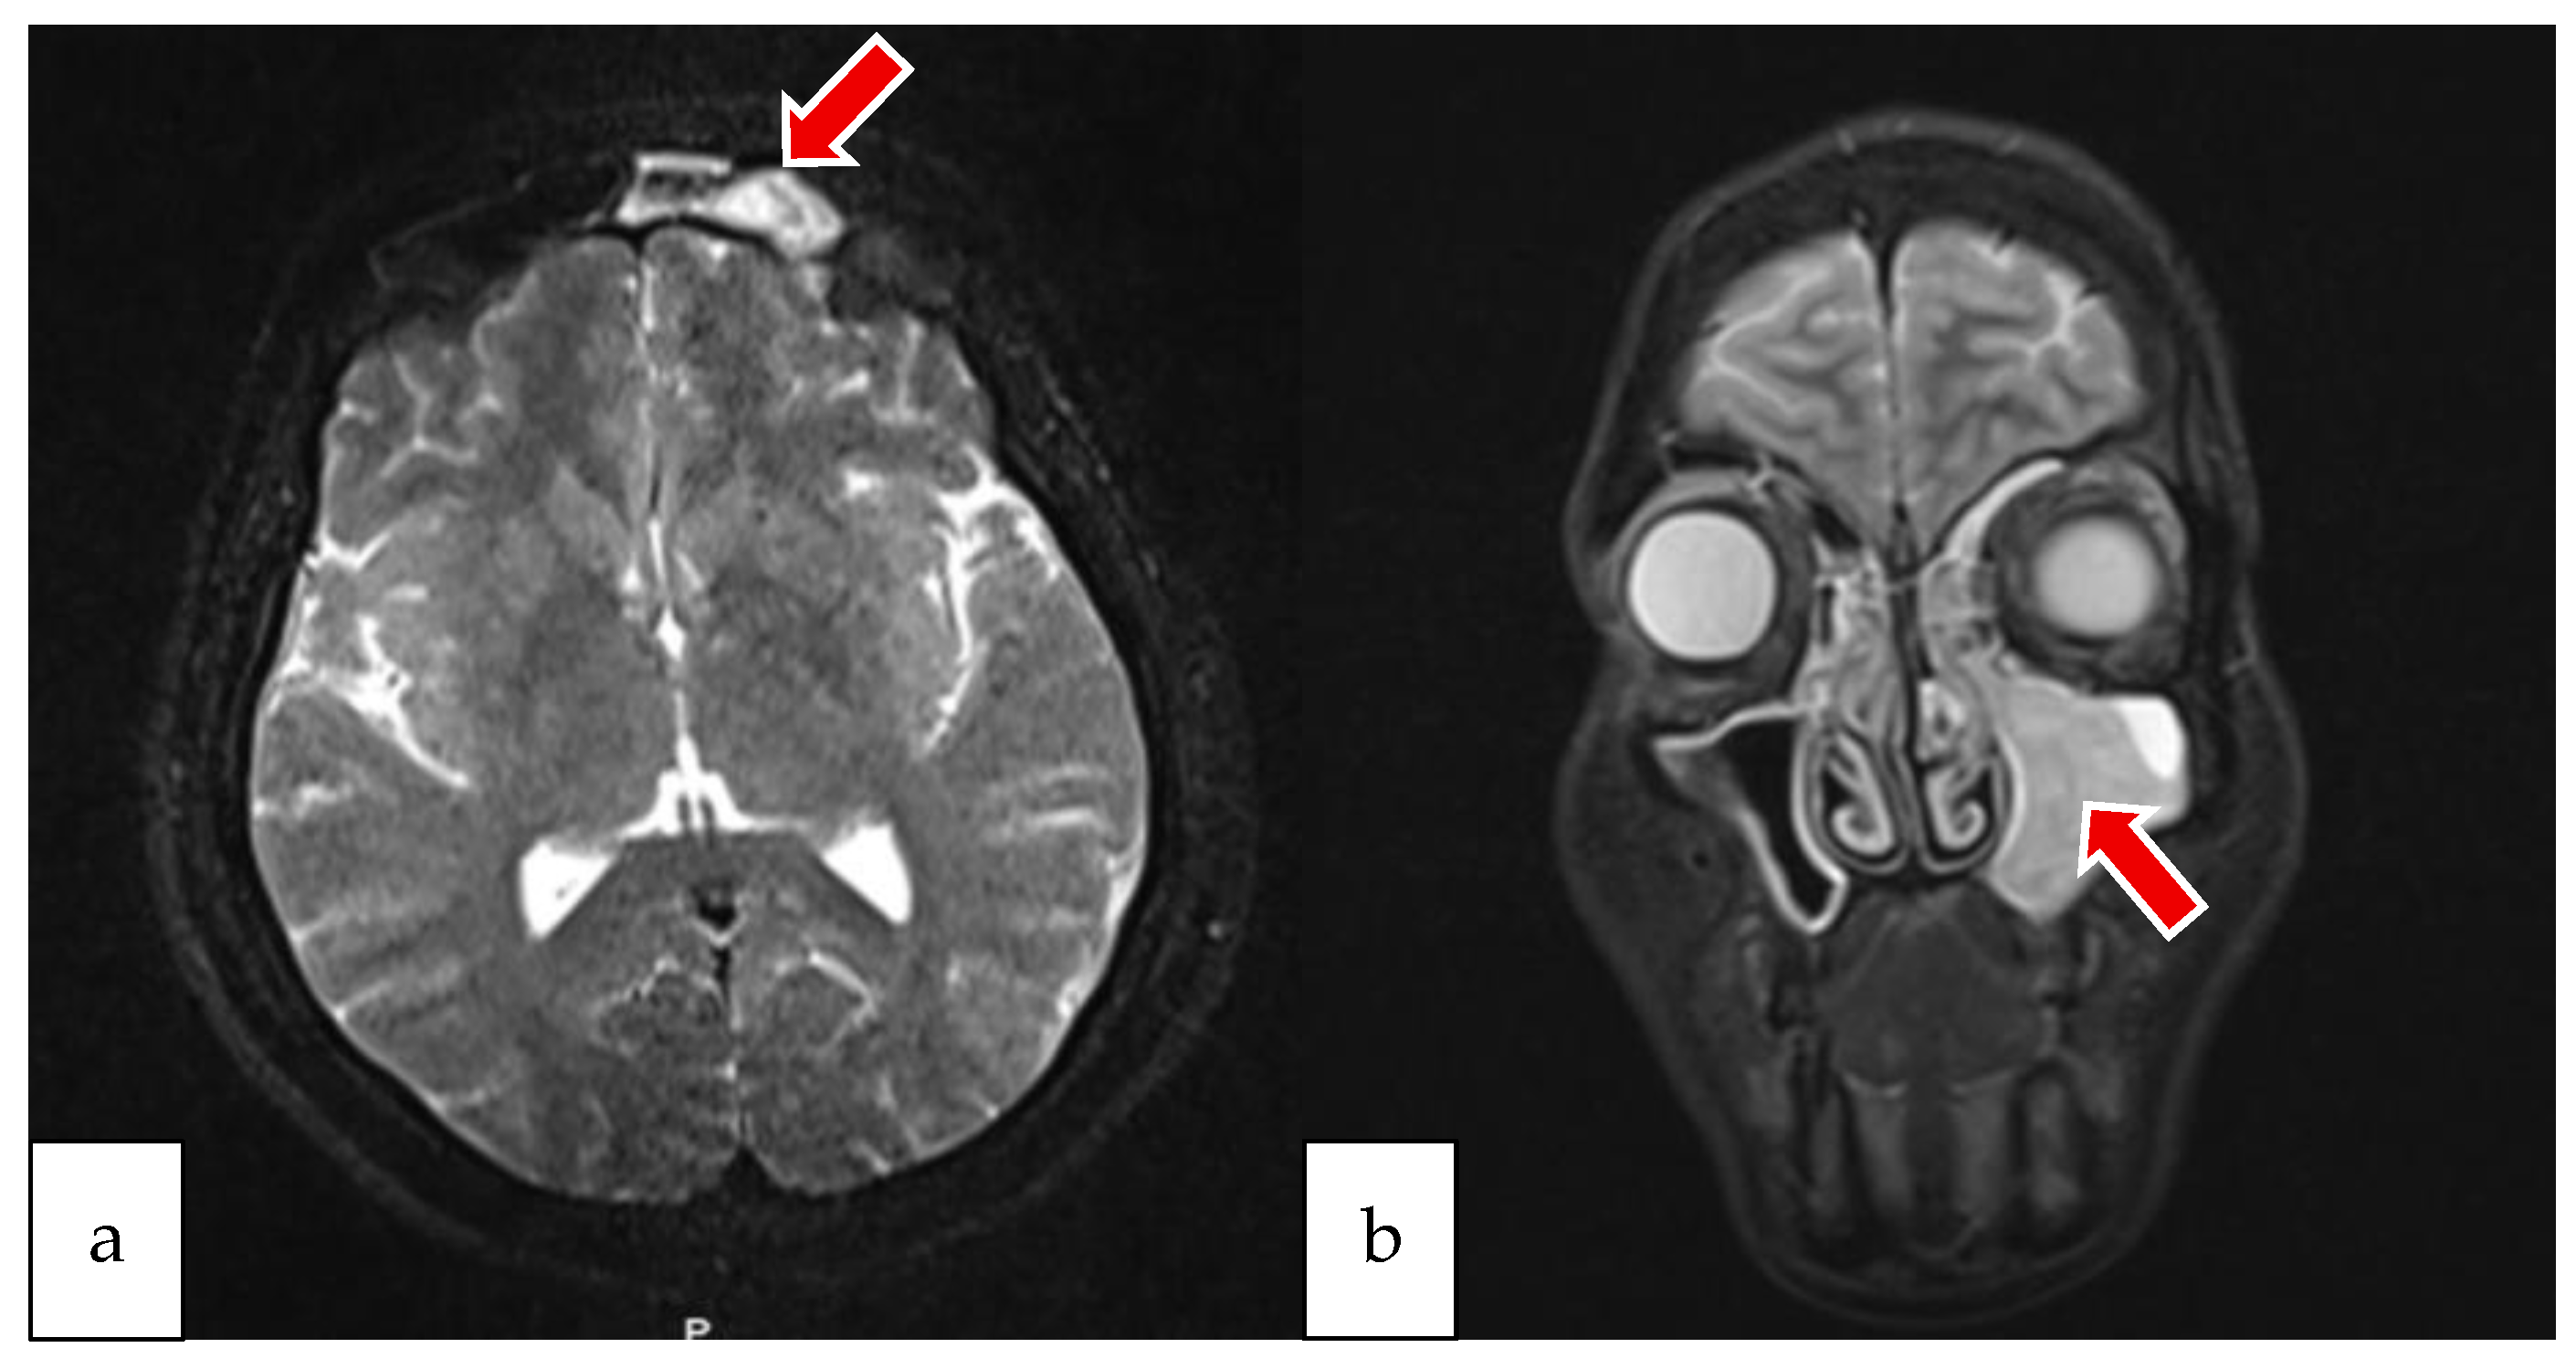

2.1. Case 1